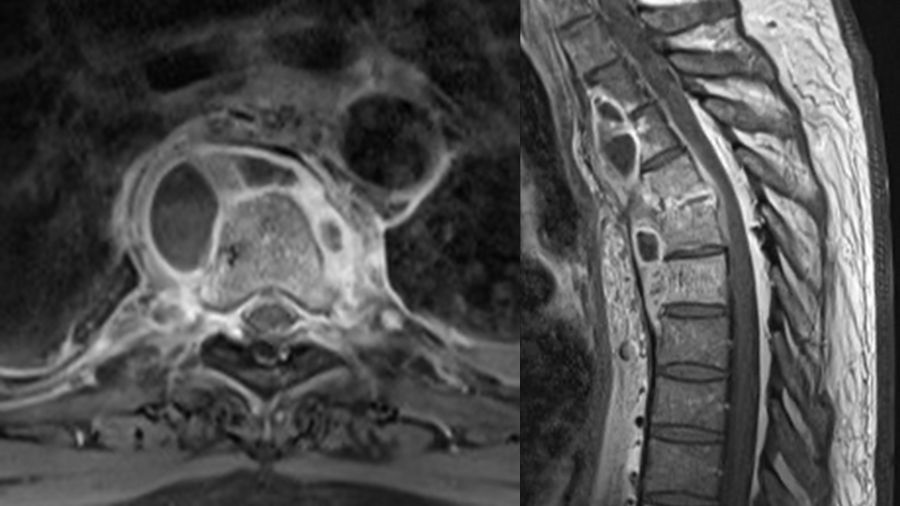

On the other hand, an MRI with a gadolinium contrast injection is really helpful in identifying the contrast media uptake around damaged tissue so called rim enhancement. Protection of disc space is another MRI finding of the spinal TB. For patients with late diagnosed Potts, you will often see epidural abscess formation together with the destruction of the vertebral bodies, which TB tends to attack because of its very strong blood perfusion.